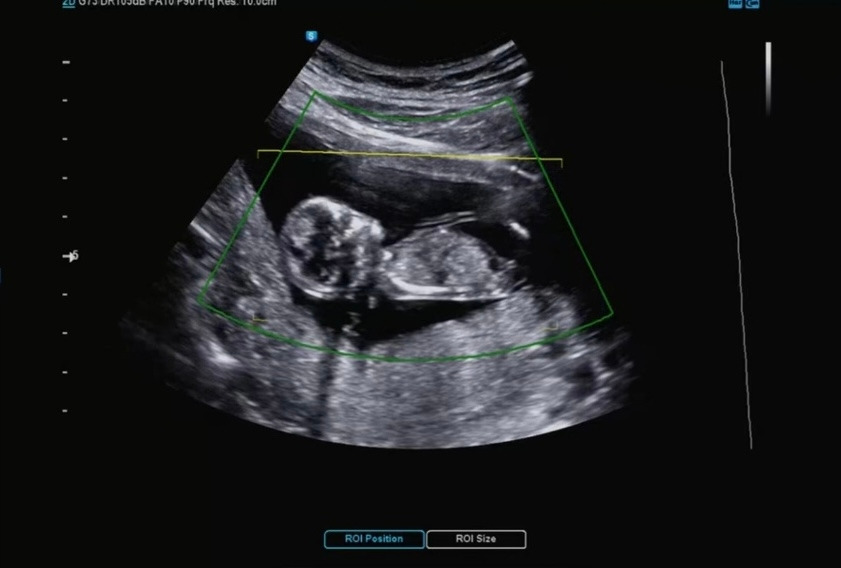

12주 차가 되었고 1차 기형아 검사를 받으러 다녀왔다.

12주 차면 아직 생식기가 완전하게 발현한 상태가 아니라 아가의 성별을 알 순 없지만 가끔 두드러지게 발현할 경우 알 수도 있다고 후기들을 보았다. 그리고 각도 법을 통해 어느 정도 예측이 가능하다고 했었기에 나와 남편은 꽤나 12주 검사를 기대하고 있었다.

계속되는 변비로 푸룬을 먹고 있었으나 가스가 너무 차는 바람에 고생을 하고 있었다. 초음파 역시 가스가 너무 많아서 잘 보이지 않는다고 선생님께서 말씀해 주셨다. 게다가 다올이가 자세를 잘 잡아주지 않았다.

선생님께서 조금 누르면서 봐야겠다고 했고, 다행스럽게도 다올이는 자세를 요리저리 바꿔주었다.